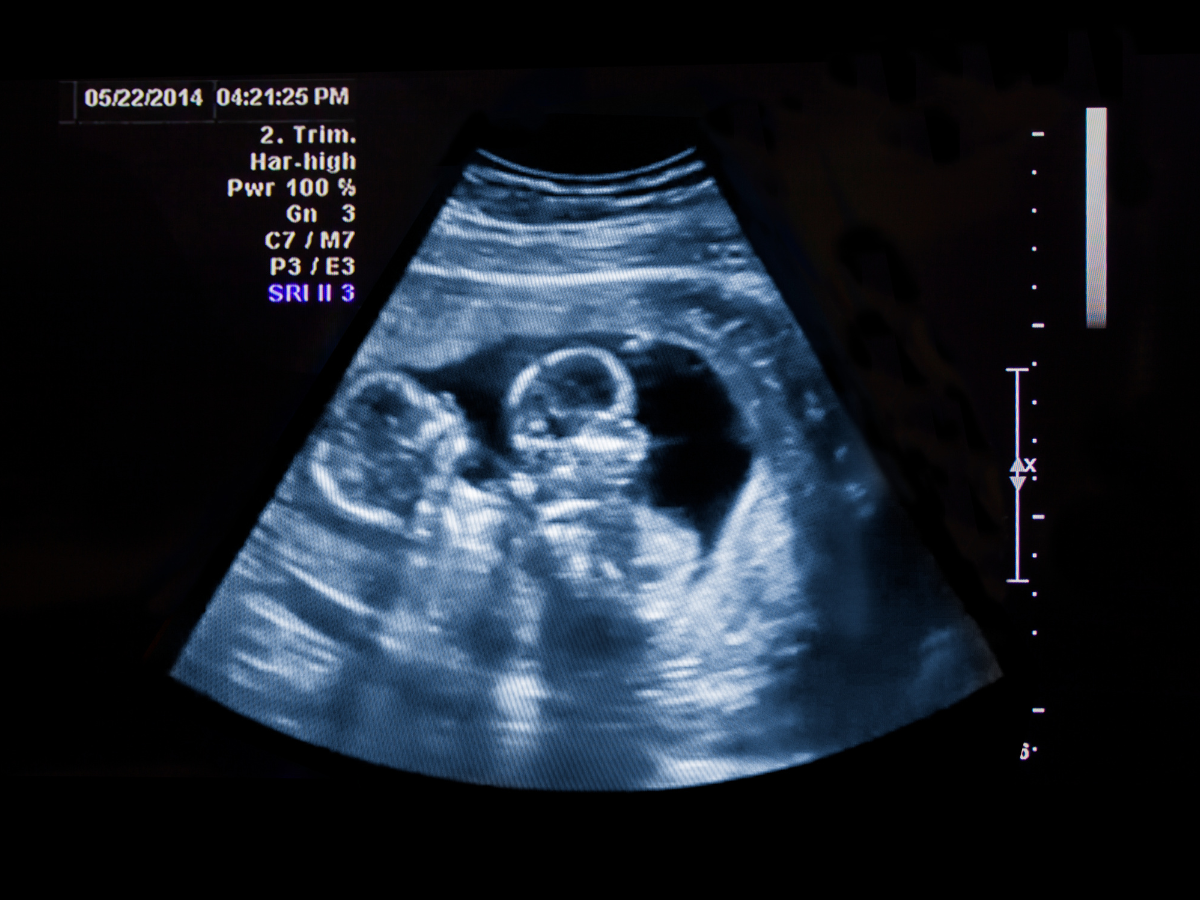

16 Week Twin Ultrasound